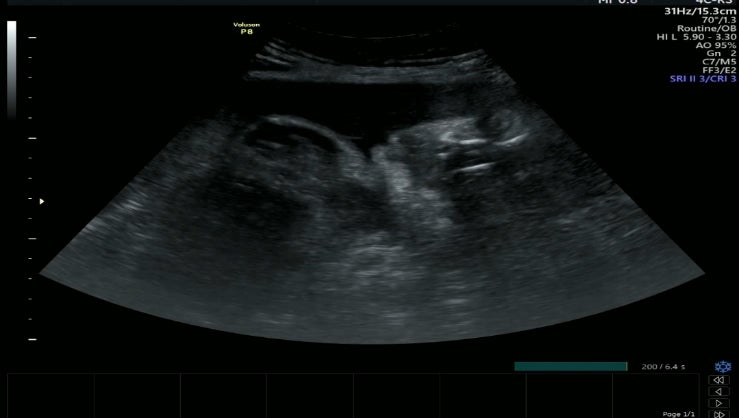

34w 0d 정기검진

34주입성 초음파보는데 눈뜨신 2.4키로 입도 오물거리고 눈도 깜빡이고 뭐가 그렇게 궁금했니 신기했다 볼...